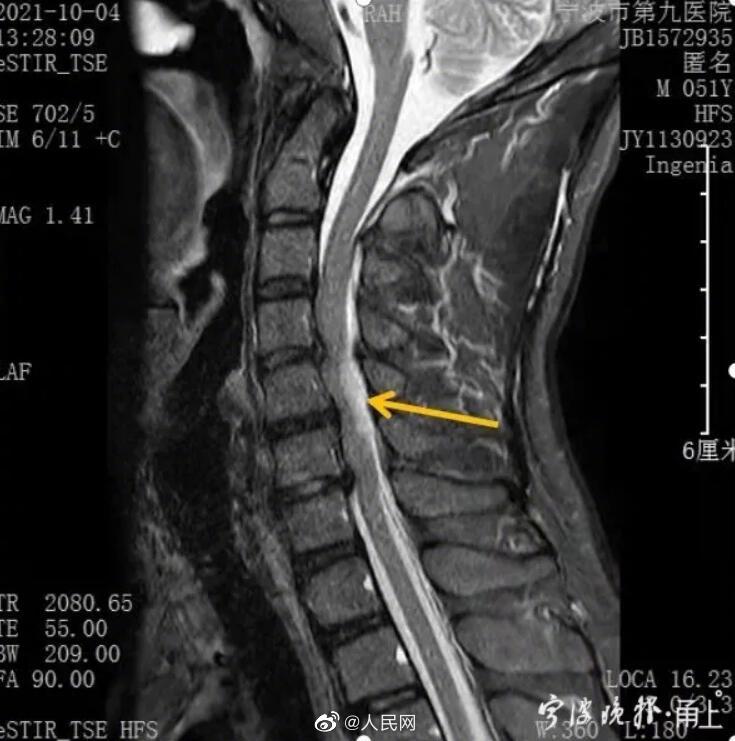

近日,宁波。50岁的张某跟同事一起搬拉重物,突然颈肩部疼痛。2小时后,张某全身失去知觉。张某被确诊为无骨折脱位性的颈脊髓损伤,又叫甩鞭样损伤。医生:甩鞭样损伤,是颈椎受到惯性外力作用,像鞭子甩出去一样而导致的损伤,严重可瞬间致命。低头族,久坐不动,缺乏锻炼、不正规的按摩,不恰当的运动等,都容易导致甩鞭型颈髓损伤。(宁波晚报)

宁波男子肩颈疼痛,2小时后全身失去知觉!医生:严重可瞬间致命!平常这些举动很危险…